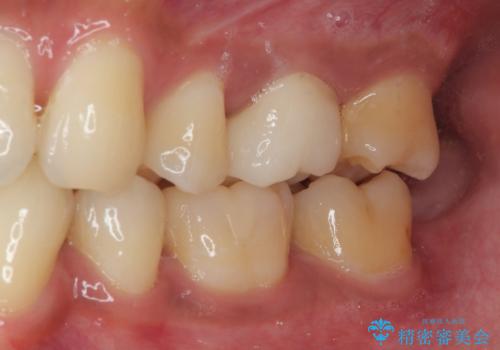

- 銀歯を外したいとのことで来院された患者様です。検査の結果、メタルインレーの範囲も大きいためオールセラミッククラウンにて補綴治療を行っていくことにしました。

拡大鏡視野下でメタルインレー、虫歯の除去を行いオールセラミッククラウンに適した形に整えました。

違和感が全くないと喜んでいただきました。